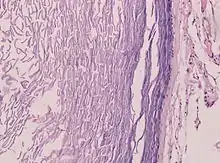

الكيسة البشرانية (بالإنجليزية:Epidermoid cyst) هي عبارة عن كيسة حميدة توجد في الغالب على الجلد وتنمو من نسيج الأديم الظاهر. بالنسبة للفحص النسيجي، تتكون الكبسة من طبقة رقيقة من الخلايا الظهارية.

يتم تشخيص الكيسات البشرانية عندما يلاحظ الشخص وجود بروز على الجلد مما يجعله يلجأ لأخذ رأي طبي. التشخيص التأكيدي يتم بناءاً على الفحص المجهري للكيسة بعد الاستئصال بواسطة اختصاصيوا الباثولوجيا، حيث تظهر الكيسة مبطنة بظهارة القرنية وتحتوي على كيراتين صفاحي بدون وجود تكلسات.